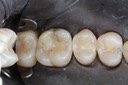

Mark Chun #13 pre-op

Mark Chun #13 composite removal